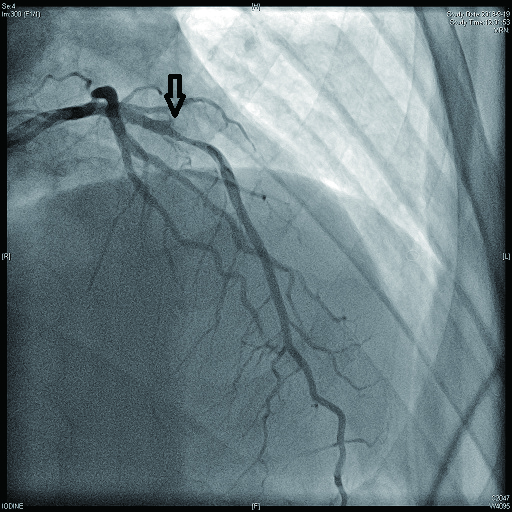

病例4 3 LAD中段及D1(图 11 LAD 85%及D1闭塞 0级 LAD中段植入支架1枚

图 11 病例4冠脉造影示LAD狭窄,D1闭塞